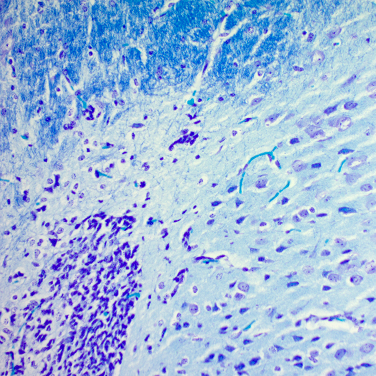

El Kit Luxol Fast Blue (según Kluewer-Barrera) se utiliza para detectar mielina y cuerpos de Nissl en secciones histológicas y para visualizar la estructura básica del tejido cerebral y de la médula espinal

Mielina - azul turquesa

Núcleos de neuronas y células de la glía - rosa a púrpura

Cuerpos de Nissl - rosa pálido